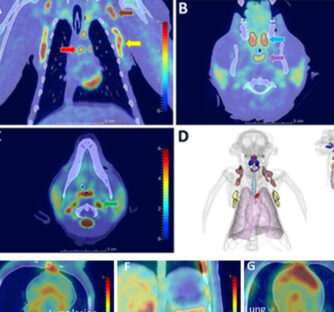

Sars-Cov-2 model to follow up vaccine and drug effect

Optimizing immunoPET imaging of tumor PD-L1 expression